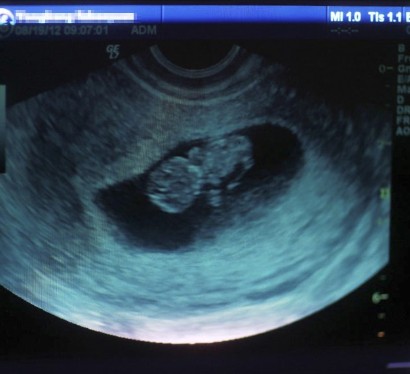

三分钟,可以做什么?听到这句话,相信很多人都知道这是什么广告。据统计,我国每年有约1300万人次的人工流产,其中约一半为重复流产。

三分钟,可以做什么?三分钟,只能喝1/3杯咖啡;三分钟,只能吃1/2个苹果……很多人最初看到这则广告时不以为然。当短短几年后,连小孩组词都会说“无痛的人流”时,人们才发现,巨大的利益和故作轻松的暗示,已经把最初还要单位开证明的补救手术,变成了某种流行选择。据统计,我国每年有约1300万人次的人工流产,其中约一半为重复流产。

在过去的十年内,无痛人流,她的医院做了很多。“没有详细、精确地统计过,但6万例是保底的数字,应该接近8万例左右。”取中间数7万例来算,从2004年至今,单她的医院,每年有7000人次的患者接受人流手术。换个算法,每天有差不多20个生命,在这里、在“3分钟”里,丧失掉诞生的权利。

据人民网等网站相关稿件统计,我国每年有约1300万人次的人工流产,其中约一半为重复流产。西安市卫生行政主管部门掌握的数据显示,2011年全市共进行节育手术14.3万例,其中人流6.5万余例,占45%左右;2012年人工流产接近7万例,占比超过50%;2013年超过7.5万例,占比超过55%。人流总数,每年增长超过7%。